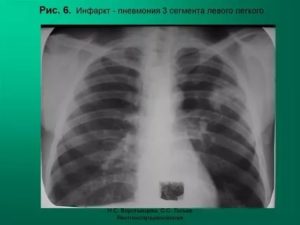

На рентгене прослеживается характерное треугольное затемнение с основанием к периферии легкого в средних и базальных сегментах. Однако, выраженный венозный застой и отек паренхимы могут сглаживать рентгенологические проявления.

Важно! При реализации рентгенографии на снимке видны затемненные области на пораженном легком.

Инфаркт легкого диагностируется с помощью рентгена, так как только с его помощью обнаруживается высокое положение купола диафрагмы, то, насколько расширены корни одного из легких, плевральный выпот, и некоторые другие отклонения.